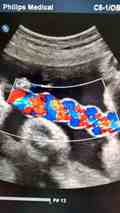

同时通过B超监测卵泡[2]的生长情况,并抽血测定雌激素含量的变化,根据结果判断调整促排卵药物的使用剂量和决定HCG注射的时间,这点和长方案是一样的。

- 3. 在应用促排卵药物的过程中采用超声监测卵泡发育十分必要,可以了解卵泡的发育情况,适时加减调整药物剂量。如条件允许,还要检测血清激素水平辅助观察卵泡的发育。因此,患者需要间隔5/3/2天不等,一般需来诊3-5次;

- 4. 当卵泡发育至10mm时,生长速度加快。此后优势卵泡大约以每日2-3mm速度增大,发育为成熟卵泡。当卵泡发育至1.7-2.0mm时,医生会根据激素水平预测排卵时间,安排你的下一步行动;

- 5. LH峰值是即将排卵的可靠指标,出现在卵泡破裂前的36小时,排卵前子宫内膜厚度可达1cm或以上;

促排卵药不可以随便服用,一定要在医生的指导下服用,否则就会对宝宝产生一些不良的影响。在服用促排卵药物之后,需要在月经的第八天到第十天开始进行超声监测,判断卵泡的发育情况以及卵泡排出的时间,这样才能让女性尽可能的受孕成功。